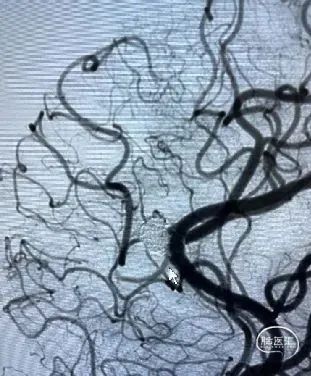

DSA:左侧大脑前动脉A2-A3动脉瘤(分叶状)

![]() 后循环造影